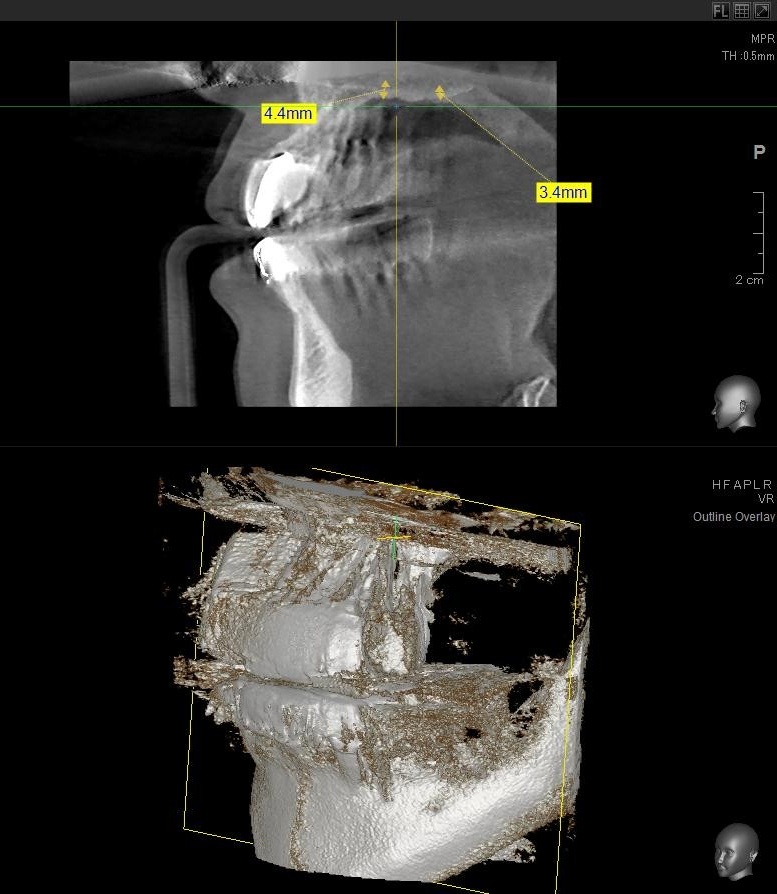

今回の患者様はインプラント植立を希望され、左上6番目・7番目の2本の植立が決まりました。

しっかりとインプラント埋め込まれた後は、動揺がないか、噛んだ時に当たらないかなどを確認して、最後にパノラマ写真を撮影して今回のオペは終了となりました。